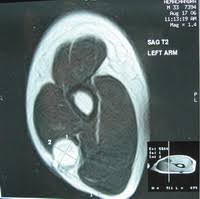

DX: Schwannoma of the upper limb (preliminary)

This is the conslusion of the case. Patient underwent MR because of US findings consistent with a heterogeneous hypoecoic mass with partial vascularity, sharp edges, within triceps and biceps brachii muscles along the median or ulnar nerve in the medial plane of the upper arm. Long axis shows that it presumptively comes from neural origin because fibers attached in cephalic and caudal position of the mass.

MR shows displacement of brachial artery and vein so neural origin has to come in consideration. It is moderate iso-hyperintense on T1 with moderate Gd-DTPA uptake.

CASE 20: 12 y/o girl with left arm palpable mass

This case remarks the importance of the ultrasound. Patient came with history of palpable mass in the medial aspect of distal arm. Physician suspected an abscess but no recent trauma or infection whatsoever.

I suggested an MR due to US findings, so here are the relevant slices: